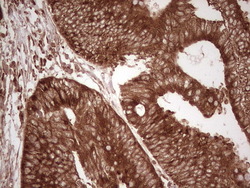

- Submitted by

- OriGene (provider)

- Main image

- Experimental details

- Immunohistochemical staining of paraffin-embedded Adenocarcinoma of Human colon tissue using anti-WIBG mouse monoclonal antibody. (Heat-induced epitope retrieval by 1 mM EDTA in 10mM Tris, pH8.5, 120C for 3min, TA806496)

- Validation comment

- IHC